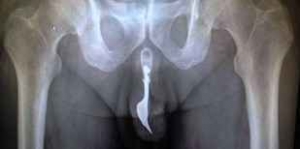

70歳のおじいちゃんがフォークをいれて抜けなくなってしまった!

なんてニュースが昔ありました。。。

【引用】imgassets.com

あと万が一、尿道に入って抜けなくなってしまったら

すぐに病院に行ってください。

抜けなくなる・・・ということは

身体に傷が付いている可能性が高いです。